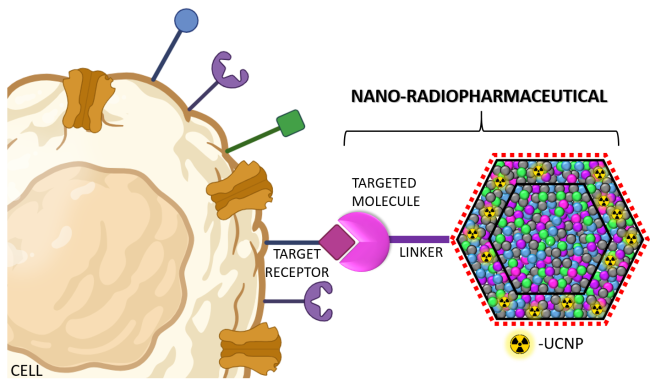

Nowoczesne nano-radiofarmaceutyki do diagnostyki i terapii

Dr Karolina Zajdel z Narodowego Centrum Badań Jądrowych otrzymała w ramach programu SONATINA Narodowego Centrum Nauki finansowanie niezwykłego projektu. Wraz z zespołem stworzy ona uniwersalne nano-radiofamaceutyki, które umożliwiały będą zarówno wykrywanie, jak i selektywne niszczenie komórek nowotworowych.